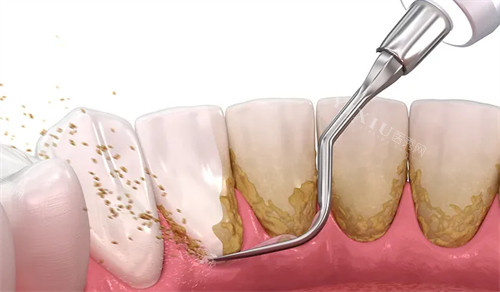

天津市北辰医院口腔科洗牙价格表

洗牙:69 - 2329 元起

超声洗牙:69 - 150 元起

洗牙(一般):794 - 993 元左右